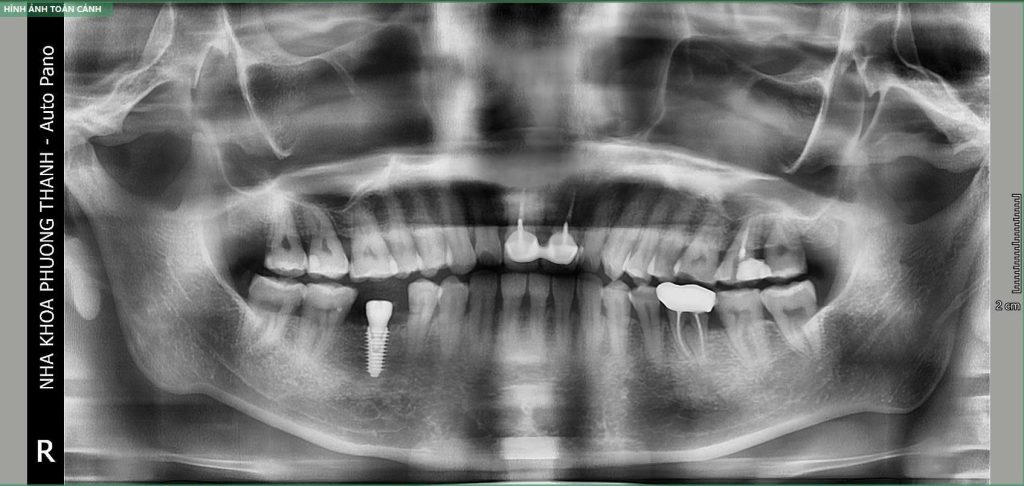

- Có thể sử dụng các phương tiện chẩn đoán hình ảnh để xác định vị trí và cấu trúc xương hàm.